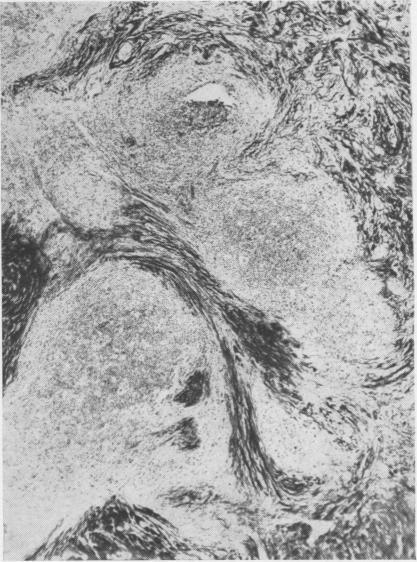

Hand-Schüller-Christian disease; report of a case with unusual lung changes.

Thorax. 1955 Dec;10(4):314-20. doi: 10.1136/thx.10.4.314.